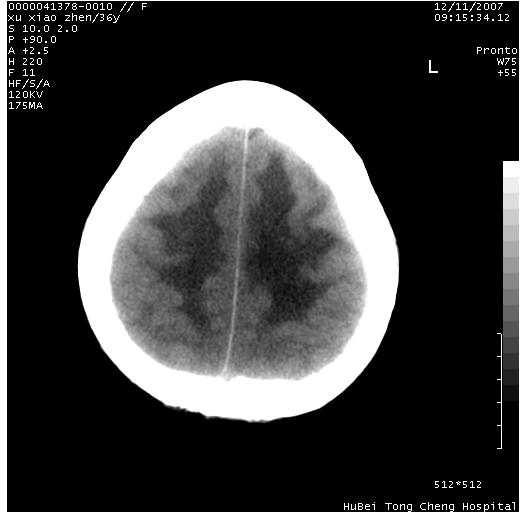

以下是引用wzr在2007-12-12 18:58:00的发言:[br]以脑白质受累,脑肿胀明显,脑室变窄,多考虑炎性改变,建议进一步ce或mri明确.

以下是引用wqs571018在2007-12-12 19:48:00的发言:[br]脑白质受累,脑肿胀明显,脑室变窄,多考虑炎性改变,脑膜炎可能性大;建议mri明确.。